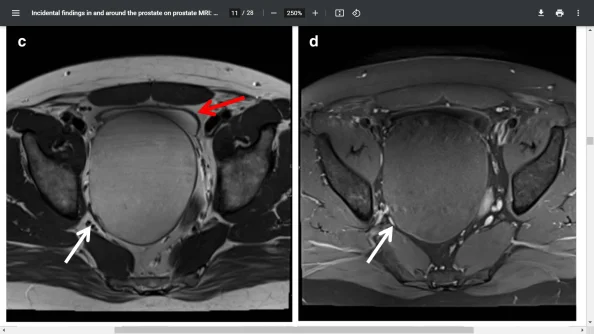

Bladder wall thickening and hydrocele

Inguinal hernia